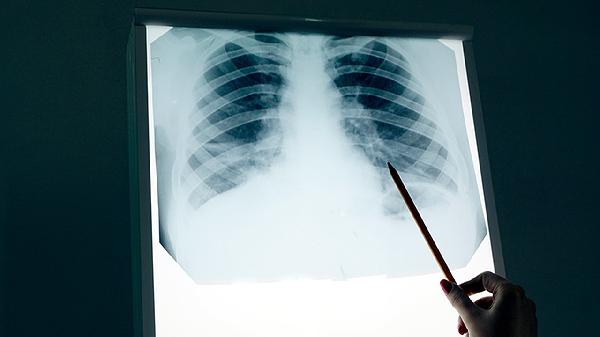

1、高危人群每年一次低剂量CT

45岁以上吸烟者、有家族史者等,低剂量CT能发现早期微小病灶。

胸片检查虽然对早期肺癌敏感性不高,但仍是基础筛查手段。